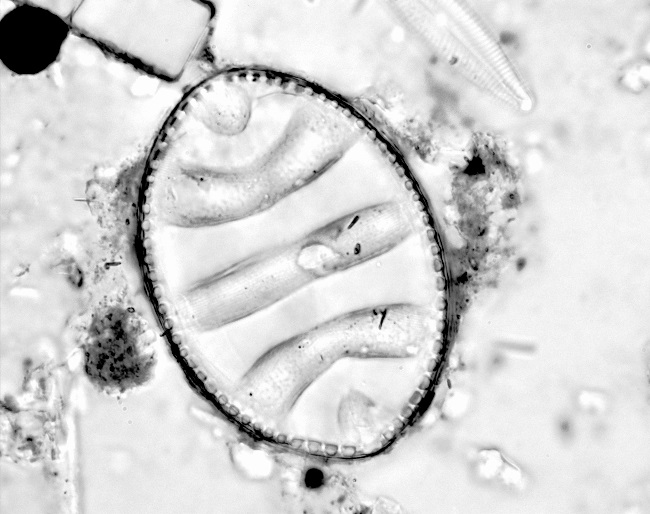

Les diatomées sont des algues microscopiques unicellulaires, qui ont la particularité de posséder un squelette siliceux résistant à la putréfaction et aux traitements chimiques. Leur taille varie de quelques µm à plus de 500 µm. Ce sont des marqueurs biologiques spécifiques d'un milieu aqueux. On les retrouve isolées ou en colonies aux formes variables :